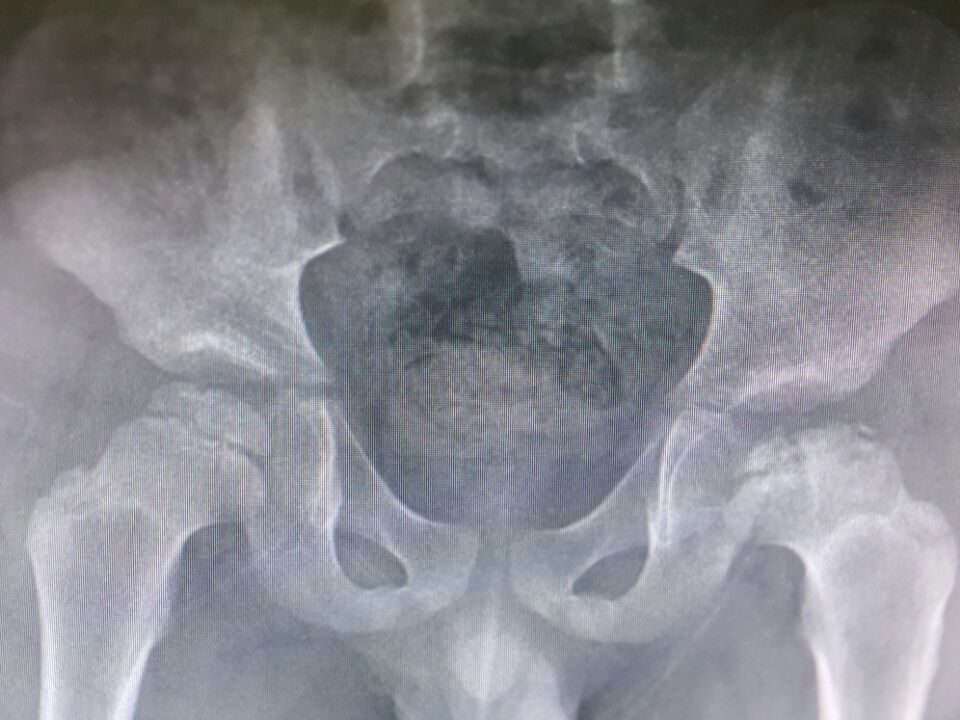

Kalça Çıkığı

KALÇA ÇIKIĞI Amaç: Toplumumuzu gelişimsel kalça çıkığı ve kalçaların normal gelişimi konusunda bilgilendirmek. Gelişimsel Kalça Çıkığı ve Kalça Gelişim Bozukluğu Nedir? Kalça çıkığı, eklemi oluşturan uyluk […]